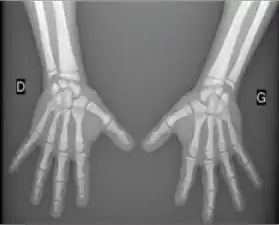

Early changes of acroosteolysis can be detected by x-ray. In this radiograph there is dissolution and fragmentation of the bone in several of the terminal phalanges.~CDC

Hand shows an acro-osteolysis of the distal phalange